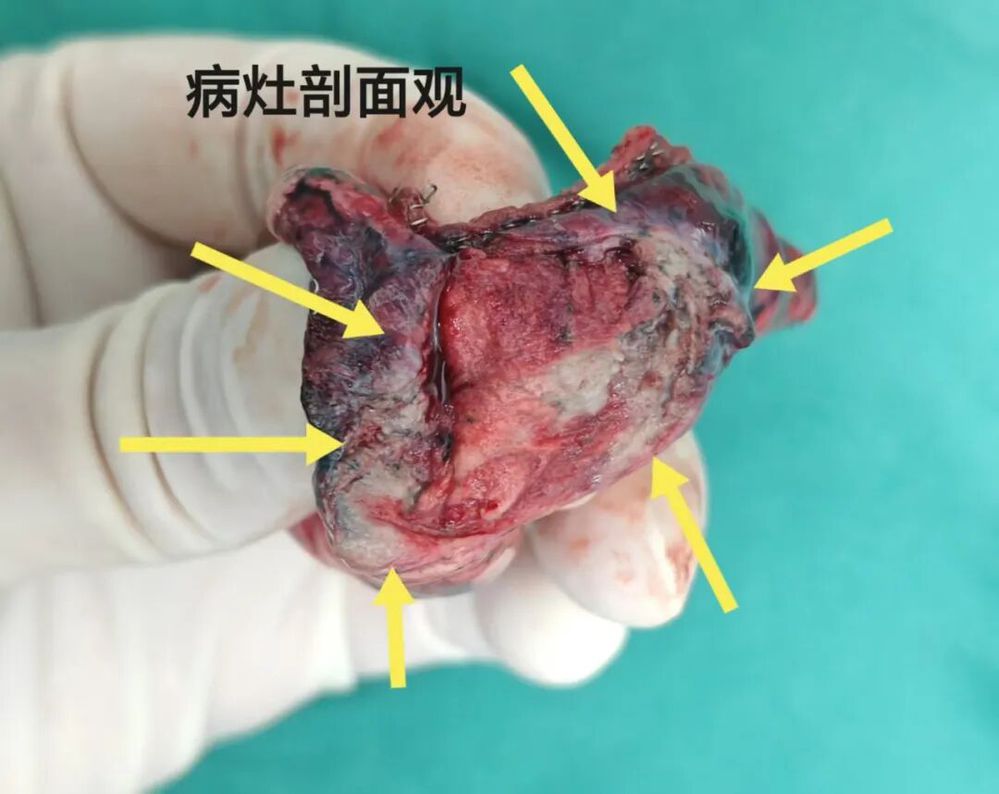

最后结果:

杭州市第一人民医院胸外科叶建明团队为其进行了单孔胸腔镜微创手术,顺利且恢复非常好。

常规病理示:浸润性腺癌,腺泡型45%,复杂腺体20%,实性型20%、乳头型10%、微乳头5%,局部间质纤维化。长径1.4厘米,低分化。切缘阴性,紧贴胸膜,但未侵犯(PL0),未见脉管侵犯。第10组及第12组淋巴结未见转移(术中探查纵隔未见明显肿大淋巴结)。